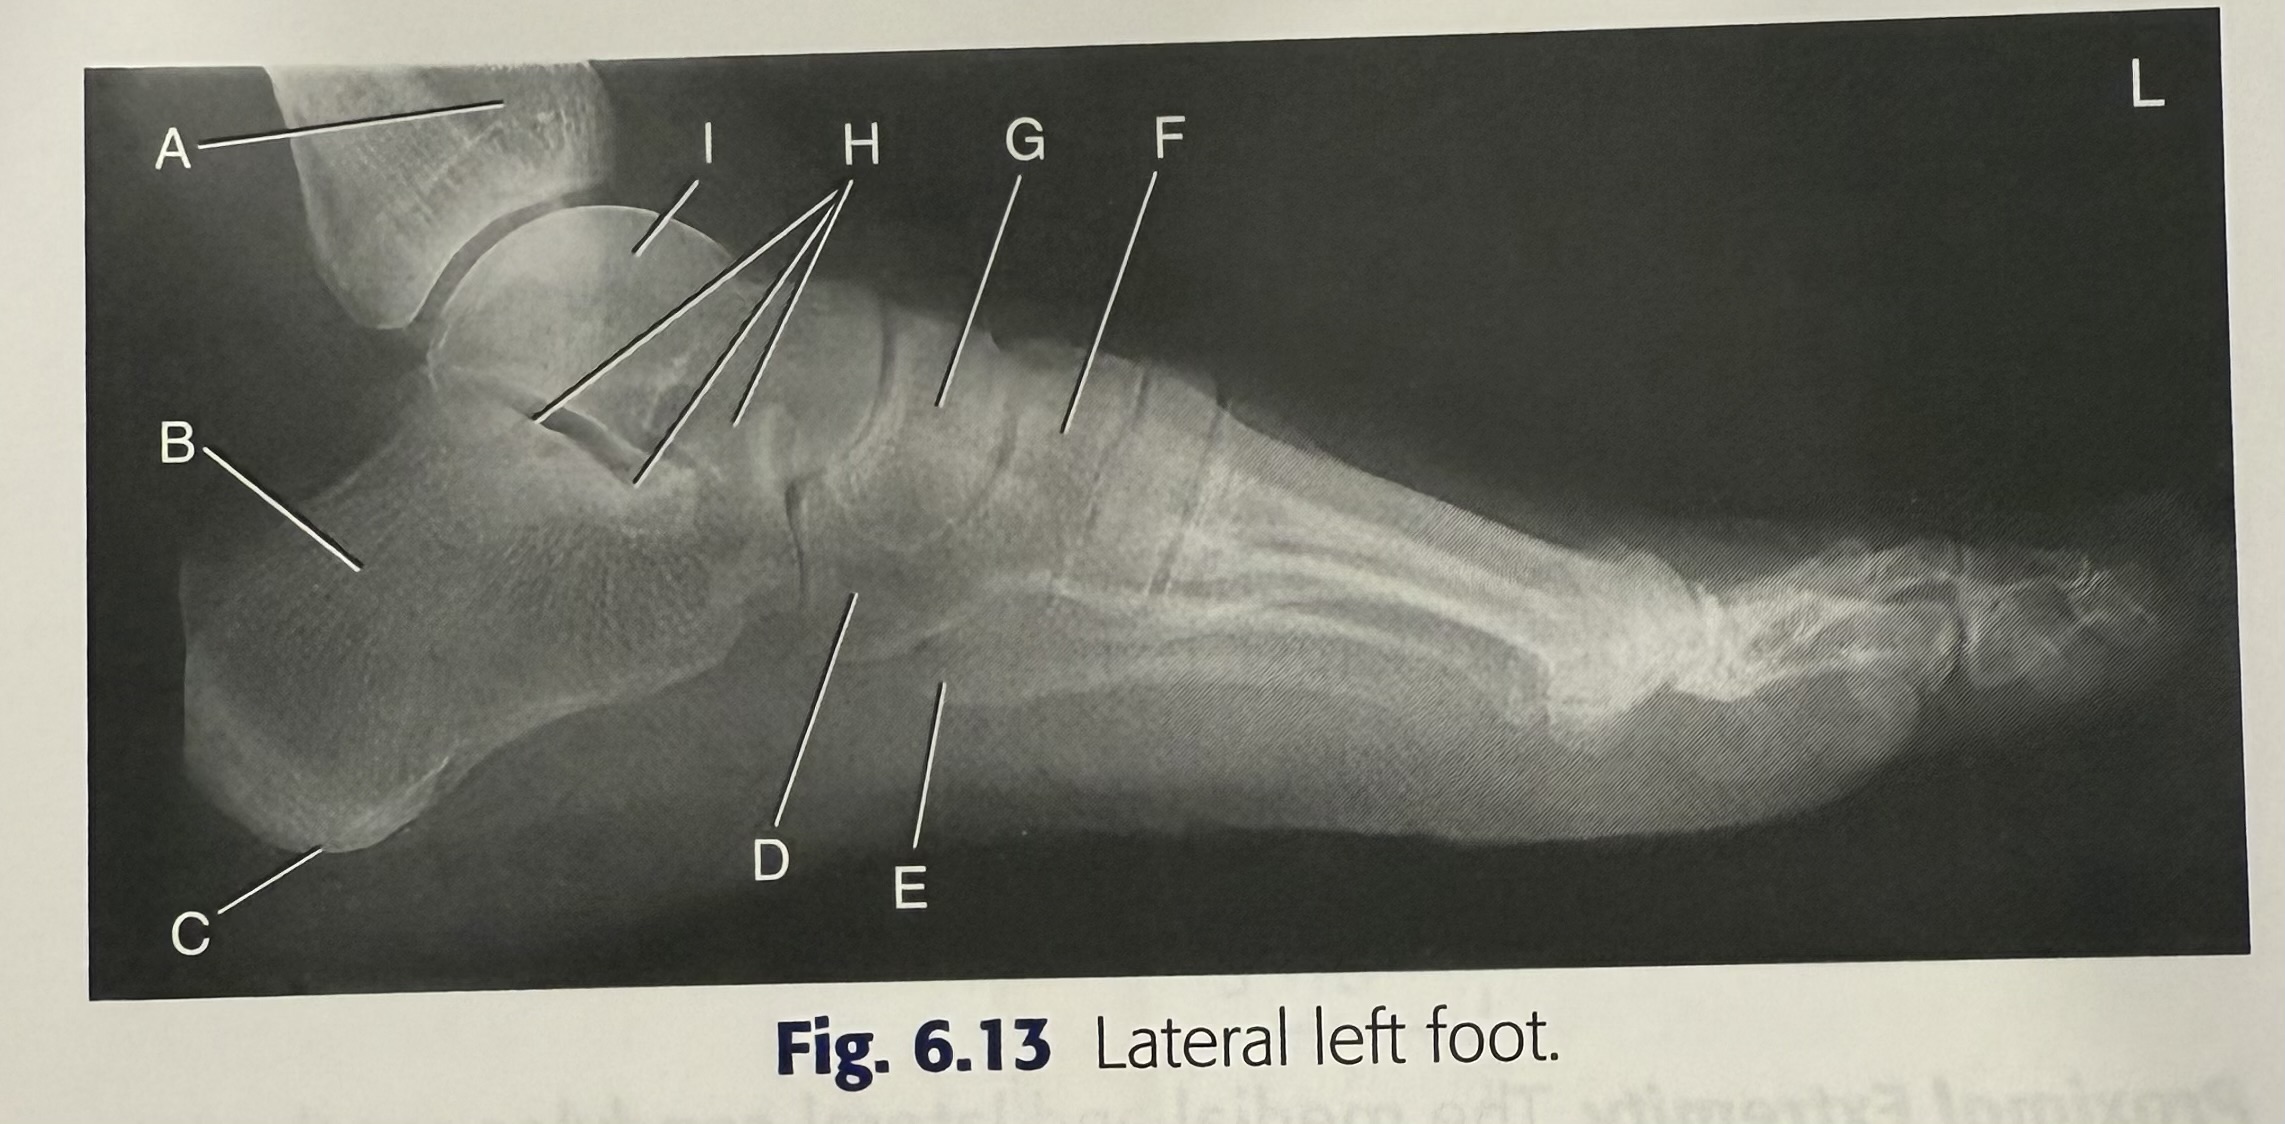

New cards

<p>H</p>

H

talus

14

<p>A</p>

A

cuboid